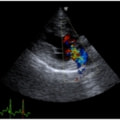

症例1:閉塞型肥大型心筋症(HOCM)【アメリカン・ショートヘア 4歳齢 去勢オス】

C:超音波写真 僧帽弁逆流と左室流出路狭窄

1年ほど前より左側胸壁からLevine 3/6の心雑音が聴取されていた。雑音の精査のため、心エコー検査を行ったところ、左室流出路の狭窄を伴う肥大型心筋症(閉塞型肥大型心筋症)と判明した。心室の拡張性を上げるため、βブロッカーであるカルベジロールを用いた治療を行っている。肥大型心筋症は犬の心疾患のように、心拡大を認めないことも多く、レントゲン写真のみで心疾患の有無を判断する事が出来ない。また、閉塞を伴わない肥大型心筋症と異なり、閉塞型の本疾患の治療に対し、Caチャネルブロッカーは推奨されない。